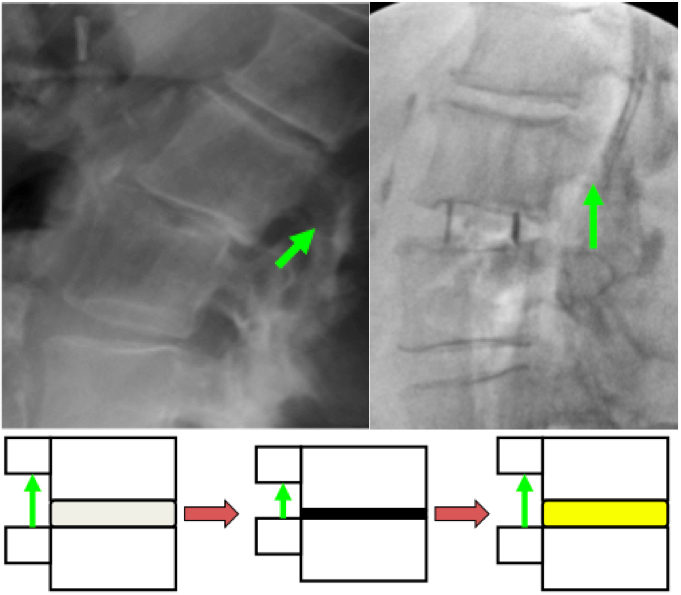

10. Oliveira L, Marchi L, Coutinho E, Pimenta L. A radiographic assessment of the ability of the extreme lateral interbody fusion procedure to indirectly decompress the neural elements. Spine (Phila Pa 1976) 2010;35(26 Suppl):S331-7. doi: 10.1097/BRS.0b013e3182022db0

12. Kepler CK, Sharma AK, Huang RC, Meredith DS, Girardi FP, Cammisa FP Jr, et al. Indirect foraminal decompression after lateral transpsoas interbody fusion. J Neurosurg Spine 2012;16(4):329-33. doi: 10.3171/2012.1.SPINE11528